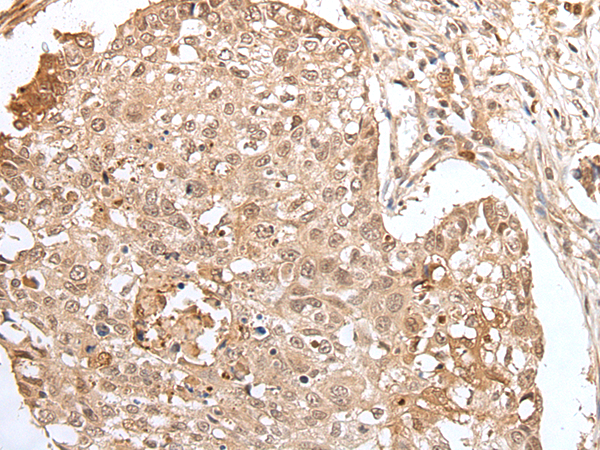

Applications:

ELISA, IHC

IHC positive control:

Human lung cancer

IHC Recommend dilution:

25-100